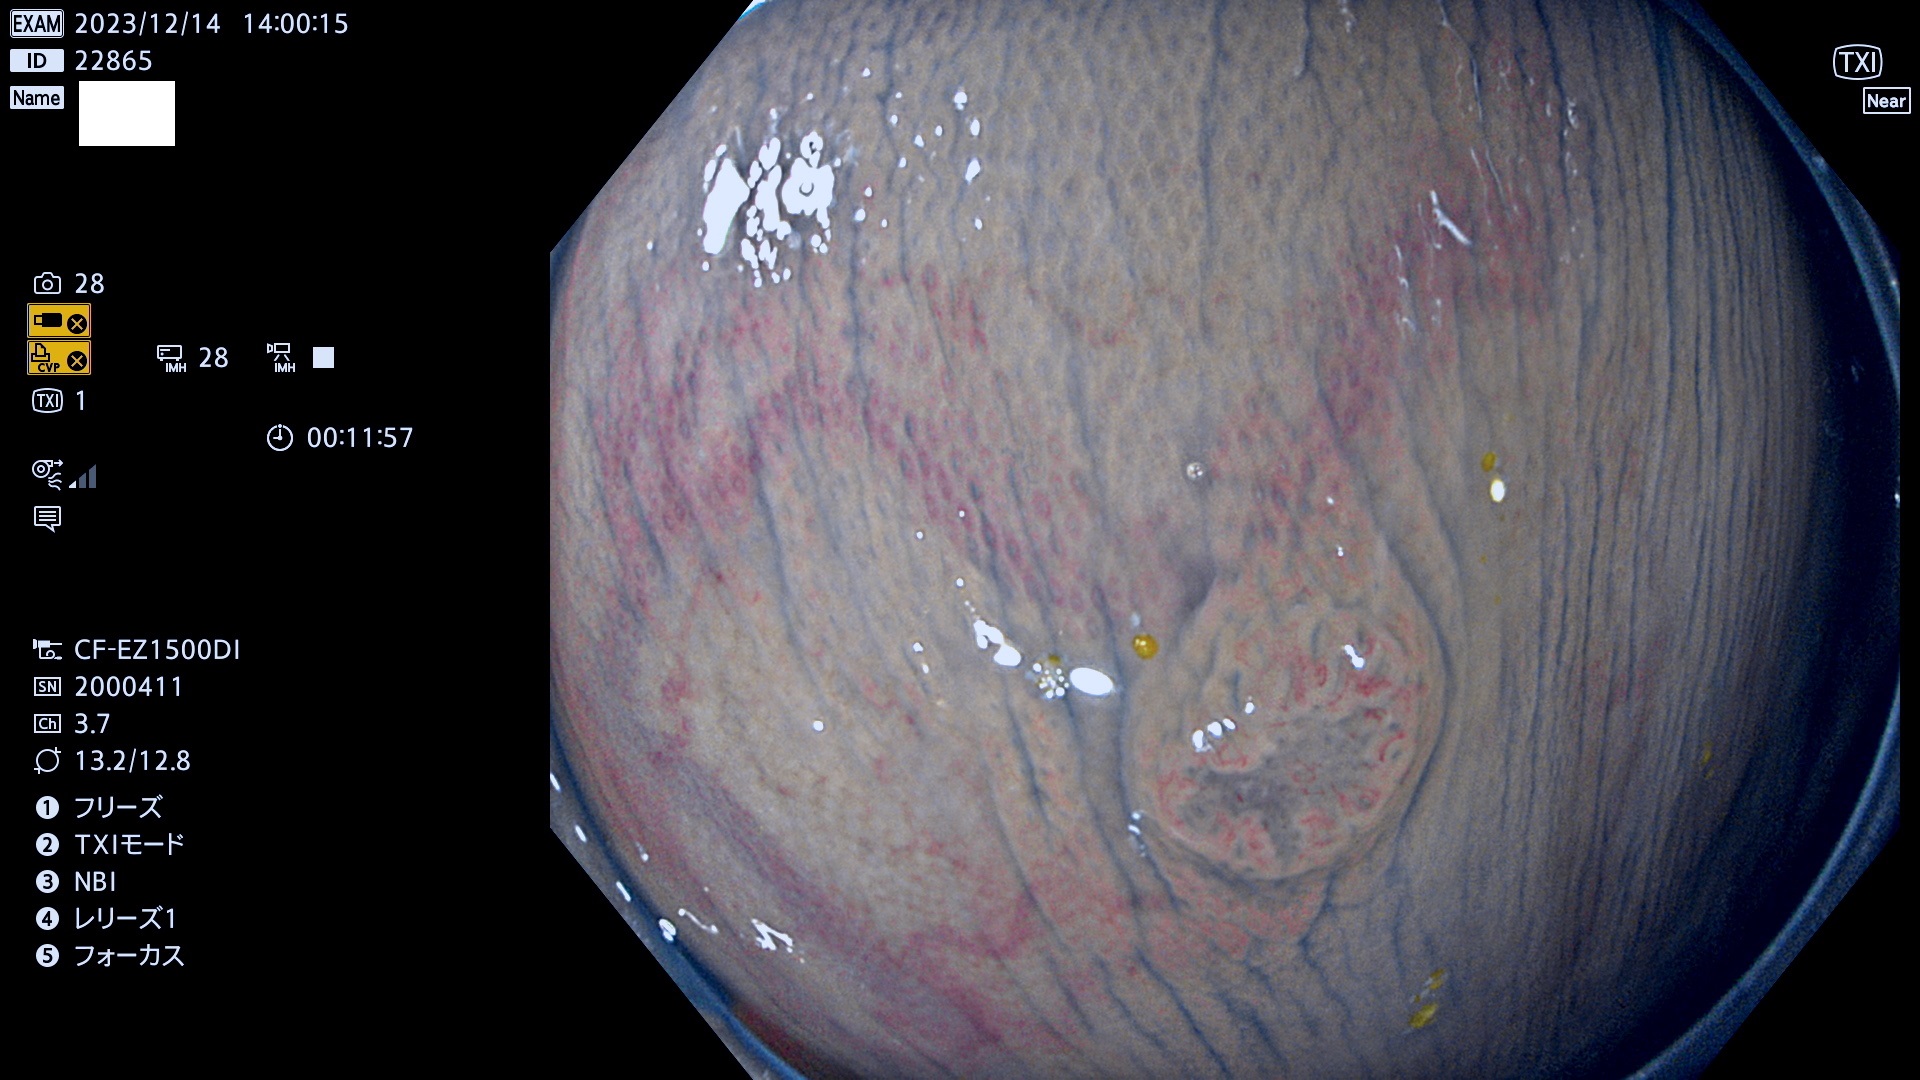

表面型腺腫(Flat Adenoma)の中で、完全に平坦な物をUb、陥凹している物をUcと呼びます。平坦隆起型(Ua)よりも、発見が難しく危険な病変です。このタイプは「内視鏡後・大腸癌の重要犯人」であり、この発見率は「腺腫発見率」よりも、重要な意味があります。

毎週の検査(木・金・土・日)に発見されたUb、Uc型・腺腫を、その週の日曜の夜にUPし1週間、提示します。

抽出の対象期間 2023年12月14日(木)〜12月18(日)の5日間(60件の検査)7件

当院で発見された炎症(ビラン)と紛らわしい腺腫